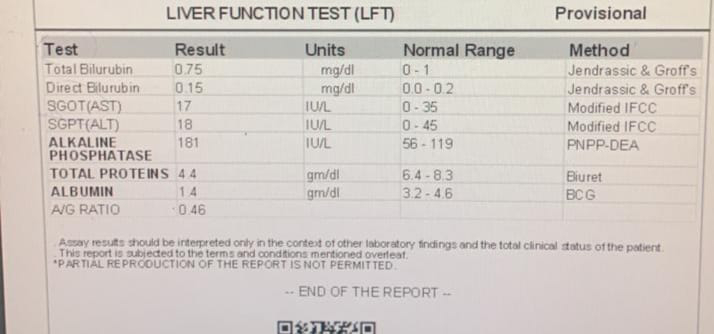

[8/5, 10:10 AM] +pajr_doctor: Sending some routines required sir PAC sir

[8/5, 12:42 PM] PaJR PHR Moderator: Even his previous OT was under spinal following which he went into delirium?

[8/5, 12:58 PM] pajr_doctor: Yes sir

[8/5, 12:58 PM] +pajr_doctor: Now they are doing it under local anesthesia

[8/5, 2:00 PM] pajr_doctor : Implant removal done under LA by doctor sir